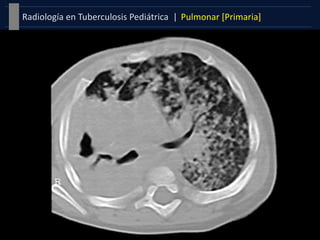

Patrón Miliar

 Patrón intersticial de una

diseminación hematógena pulmonar.

 Nódulos finos, >2mm, márgenes bien

definidos, uniformes en tamaño y

distribución, sin tendencia a confluir,

y diseminados de forma homogénea y

bilateral.

 Hiperinsuflación manifestación más

temprana (dos primeras semanas).

 El nódulo miliar puede no ser visible

en la radiografía hasta seis semanas

después.

Formas Clínicas |Pulmonar [Primaria]Tuberculosis Pediátrica | Derrame pleural  Secuela tardía de infección primaria (3-7 meses tras la exposición).  Generalmente unilaterales y ecograficamente presentan septos producidos por el exudado tuberculoso.  Patrón más característico de la en el adolescente. Patrón Miliar  Patrón intersticial de una diseminación hematógena pulmonar.  Nódulos finos, >2mm, márgenes bien definidos, uniformes en tamaño y distribución, sin tendencia a confluir, y diseminados de forma homogénea y bilateral.  Hiperinsuflación manifestación más temprana (dos primeras semanas).  El nódulo miliar puede no ser visible en la radiografía hasta seis semanas después.